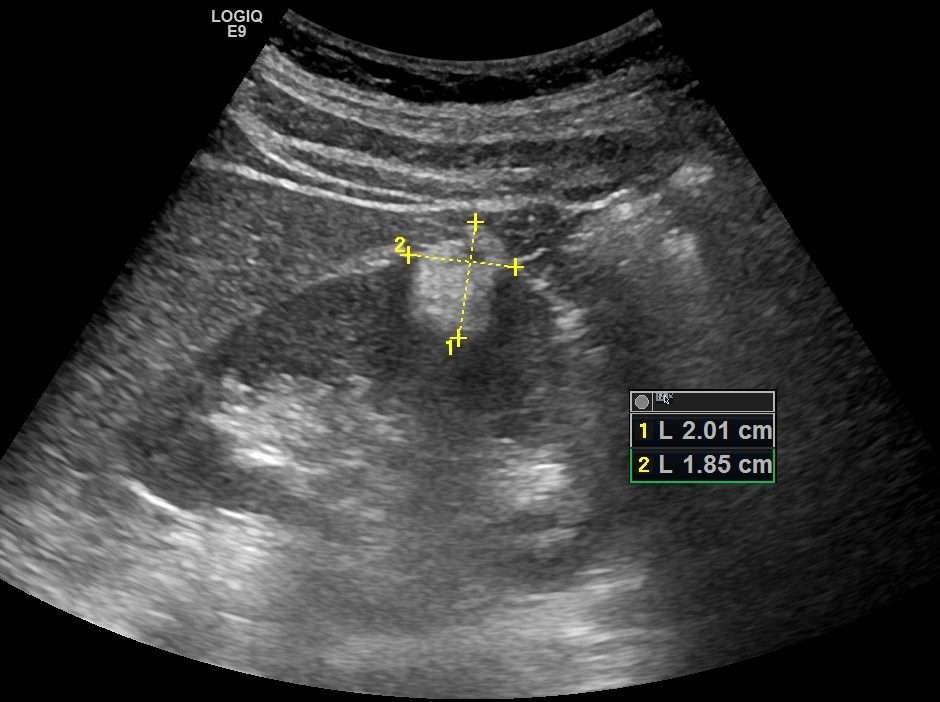

При ультразвуковом исследовании по наружной поверхности правой почки определяется гиперэхогенное образование, размерами до 20 мм, неправильной овальной формы, распространяющееся почти на всю толщину паренхимы и умеренно выбухающее за контур почки.

Рис. 01. Ангиомиолипома почки.

Контуры образования достаточно чёткие, но неровные, "дольчатые". Структура неоднородная, с мелкими гипоэхогенными включениями.